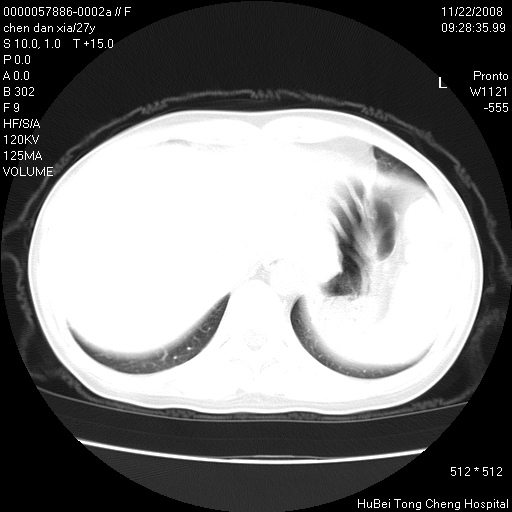

标题: CT16752:F,27Y。发热咳嗽20余天,伴盗汗。 [打印本页]

标题: CT16752:F,27Y。发热咳嗽20余天,伴盗汗。

考虑双肺粟粒性肺tb,右侧胸膜增厚.

右下肺见片絮状影,两肺野内分布不均的小结节影,结核并肺内播散可能性大,建议结合实验室检查 .

右下肺纹理模糊;纵隔可见肿大淋巴节;右心缘旁结节,边缘光滑,纵隔窗病变范围较肺窗明显小,首先考虑右下肺结核,不排外淋巴瘤

双肺纹影普多,部分呈网状,支炎或淋巴管炎?

纵隔内淋结肿

局部胸膜增厚

下肺结节,结节内钙化,肺门纵隔淋巴肿大 结核可能性大

似有粟米状结节。考虑粟粒型肺结核?

1)考虑两肺感染性病变。2)纵隔淋巴结肿大。